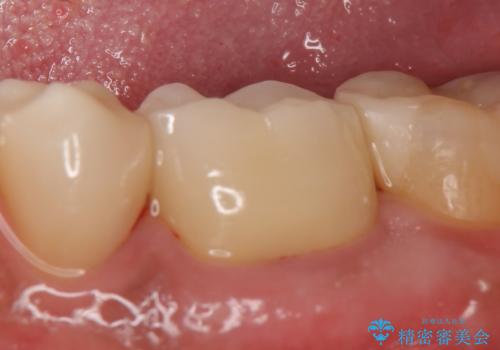

今回用いたオールセラミッククラウンはジルコニアフレームという白い素材の上にセラミックを盛っているため、審美性が非常に高いのが特徴です。

また、ジルコニアは人工ダイヤモンドの材料にも使われているほど高い強度を持っており、そのためオールセラミッククラウンは審美性だけでなく、奥歯やブリッジの補綴も可能とするクラウンです。

- オールセラミッククラウン…¥100,000、仮歯…¥10,000、ファイバーコア…¥20,000費用は治療当時の料金となります